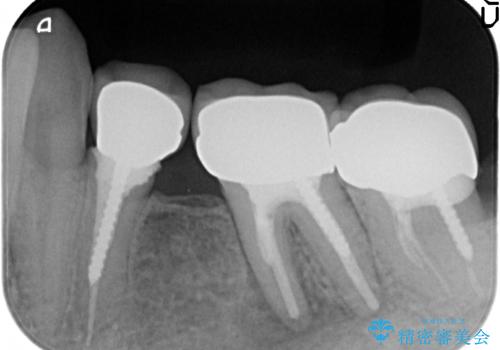

- 左下の奥歯でものを咬むと痛むので診て欲しいといらっしゃった方の症例です。

検査の結果左下6に根尖病変を認めたため、再根管治療を行いました。

その後症状の消失を確認し、オールセラミッククラウンによる補綴を行いました。